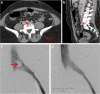

Patients with venous anomalies are at increased risk of developing venous thromboembolism (VTE) and subsequent complications, but they are often under-recognised. While unprovoked VTE may trigger testing for inherited thrombophilias and malignancy screening, anatomic variants are considered less often. Venous anomalies increase the risk due to venous flow disturbance, resulting in hypertension, reduced flow velocity and turbulence. Recognition is important as endovascular or surgical intervention may be appropriate, these patients have a high rate of VTE recurrence if anticoagulation is ceased, and the anomalies can predispose to extensive VTE and severe post-thrombotic syndrome (PTS). In this case series, we present representative cases and radiological images of May-Thurner syndrome (MTS), inferior vena cava (IVC) variants and venous aneurysms, and review the available literature regarding optimal diagnosis and management in each condition.